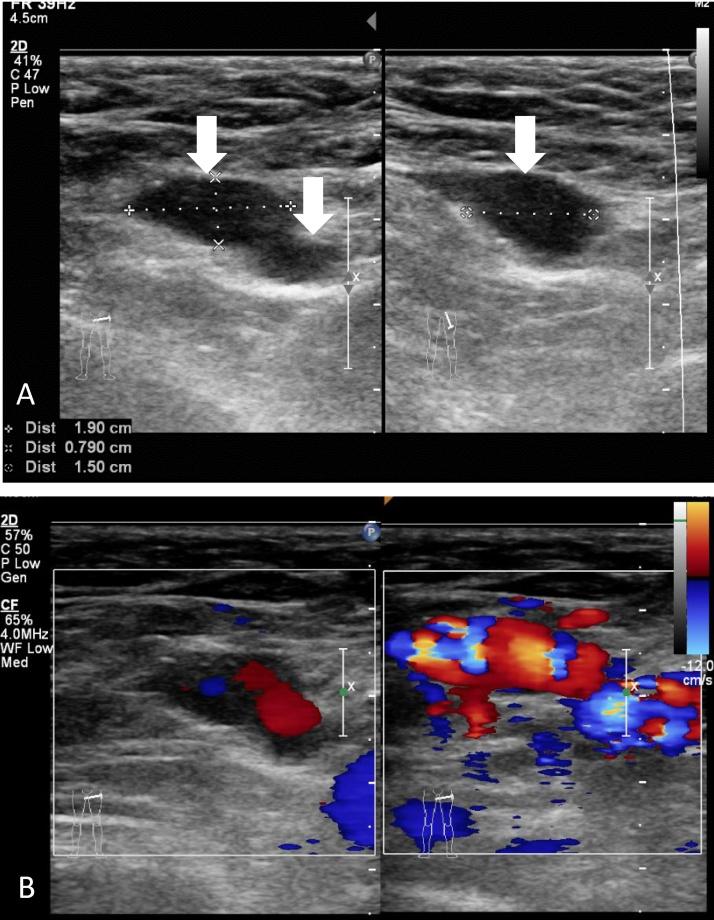

A 37-year-old Japanese woman complained of left groin swelling for 2 weeks at her 28th week of gestation of her first pregnancy. According to a physical examination, she had a soft, painless swelling in the superficial inguinal ring of the left groin. An inguinal hernia was suspected and she was thus scheduled to undergo herniorrhaphy. However, since she had varicosities in the left labia majora, she first underwent color Doppler ultrasonography and a final diagnosis of round ligament varicosities was this made. Her symptoms resolved after delivery of her baby.

We herein report 10 cases of RLV in pregnant Japanese women who were initially suspected of having an inguinal hernia. All of them were suspected to suffer from inguinal hernias after a clinical examination by their attending gynecologist. All of them were diagnosed using gray scale and color Doppler ultrasonography, treated with conservative management, and the symptoms resolved in all cases after the delivery.

This is the largest report from Asia regarding RLV. To avoid unnecessary surgery in pregnant women, surgeons must be aware of this entity make an accurate diagnosis based of the findings of Doppler ultrasonography.

一名37岁的日本女性,在其首次怀孕第28周时,因左腹股沟肿胀2周前来就诊。体格检查发现,她左腹股沟浅环处有一个柔软、无痛的肿胀。怀疑为腹股沟疝,因此安排她接受疝修补术。然而,由于她左侧大阴唇有静脉曲张,她首先接受了彩色多普勒超声检查,最终诊断为圆韧带静脉曲张。产后她的症状消失。

我们在此报告10例日本孕妇的RLV病例,她们最初均被怀疑患有腹股沟疝。她们在主治妇科医生进行临床检查后均被怀疑患有腹股沟疝。所有病例均通过灰阶和彩色多普勒超声检查确诊,采用保守治疗,所有病例产后症状均消失。

这是亚洲关于RLV的最大规模报告。为避免对孕妇进行不必要的手术,外科医生必须了解这种疾病,并根据多普勒超声检查结果做出准确诊断。